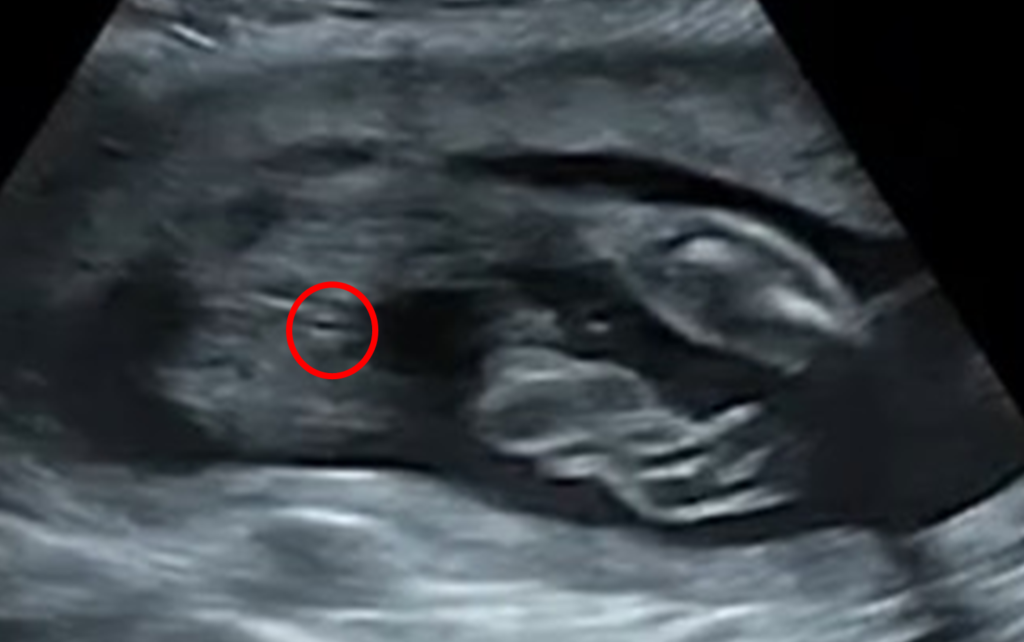

エコーでの見え方:女の子の場合

女の子の場合は、いわゆる「木の葉マーク(コーヒー豆のような形)」が見えることで判断されることが多いそうです。

一方、男の子の場合は特徴的な突起が確認できるため、比較的わかりやすいと言われています。

これが今回の性別判定のエコー写真です。

どこが「木の葉マーク」かわかりますでしょうか。

正解は、、

ここです!

ここがいわゆる「木の葉マーク」のようです。

動画で見せてもらいましたが、「木の葉マーク」がどうというよりも、明らかにおちんちんと玉がないことがよくわかります。

今回もそうした見え方が確認できたことで、「90%」という判断につながったのだと思います。